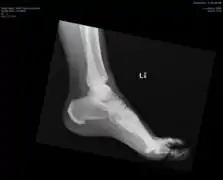

Ectopic calcification and new bone formation in diffuse idiopathic skeletal hyperostosis (DISH) Ectopic calcification and new bone formation in diffuse idiopathic skeletal hyperostosis (DISH)